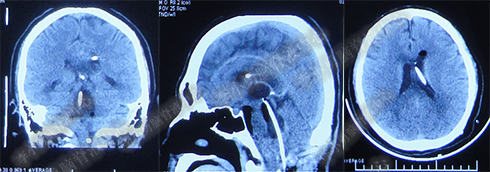

2017年6月27日(分流术后5天),复查头部CT(图-6)显示幕上脑室及第四脑室均有所缩小。

图-6:2017年6月27日头部CT

图-7:2017年7月30日头部CT

图-8:2017年9月18日头部CT

图-9:2017年10月15日头部CT